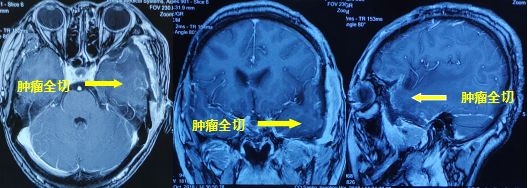

水肿消退,中线基本回位

术后恢复较好,复查核磁提示肿瘤切除满意,水肿明显消除,中线基本回位。病检结果提示血管瘤型脑膜瘤,WHO Ⅰ级。